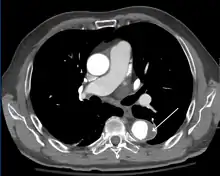

Computed tomography

Computed tomography angiography is a fast, non-invasive test that gives an accurate three-dimensional view of the aorta. These images are produced by taking rapid, thin-cut slices of the chest and abdomen, and combining them in the computer to create cross-sectional slices. To delineate the aorta to the accuracy necessary to make the proper diagnosis, an iodinated contrast material is injected into a peripheral vein. Contrast is injected and the scan performed using a bolus tracking method. This type of scan is timed to injection to capture the contrast as it enters the aorta. The scan then follows the contrast as it flows through the vessel. It has a sensitivity of 96 to 100% and a specificity of 96 to 100%. Disadvantages include the need for iodinated contrast material and the inability to diagnose the site of the intimal tear.